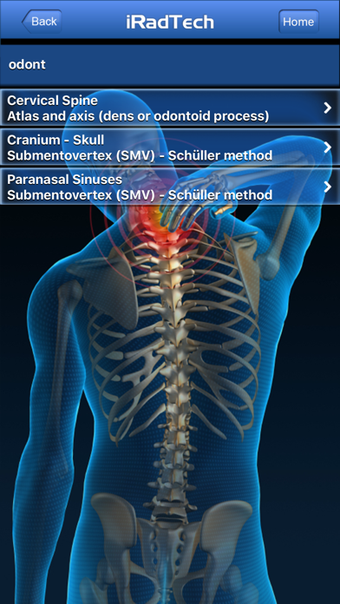

IRadTechè un programma completo per iPhone, che fa parte della categoria 'Medicina'.

Informazioni su IRadTech per iPhone